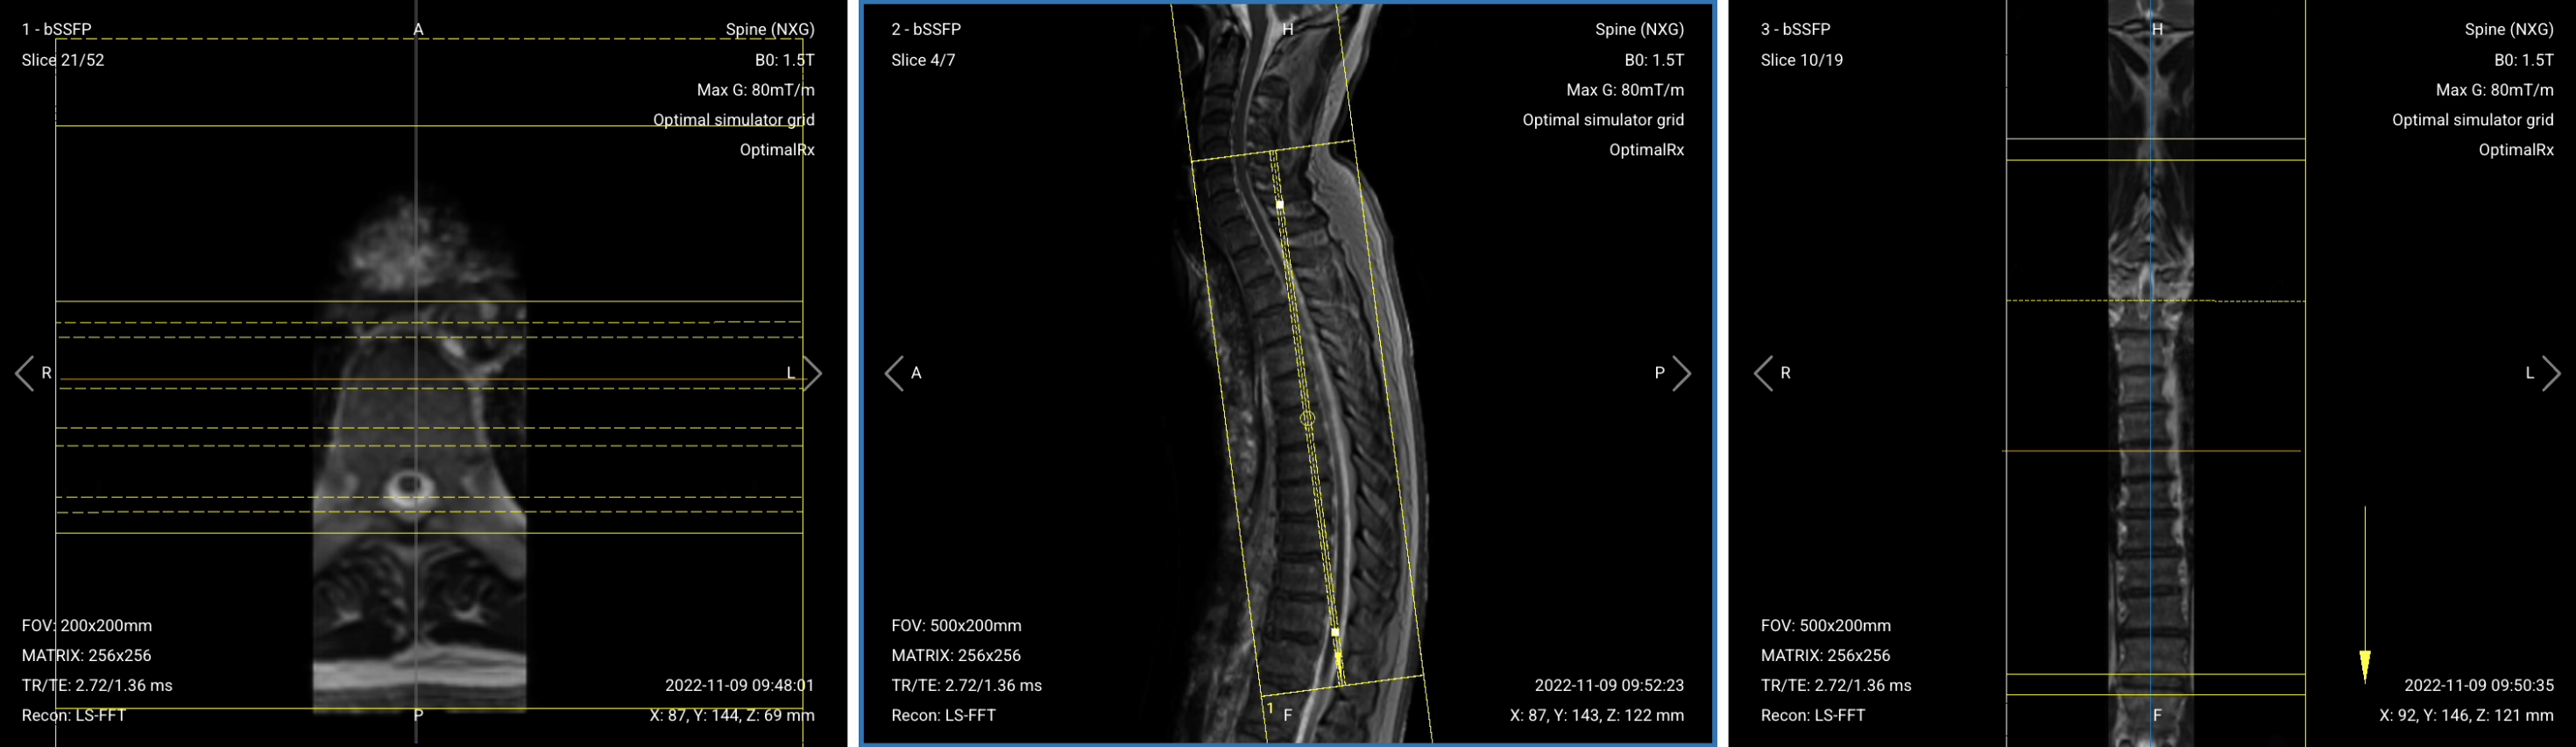

Once acquired, upload the initial localizer images into the three viewports.

Then, scroll through each of the image stacks to locate a central slice that clearly shows the anatomy of the thoracic spine.

✅ Correct Setup of Localizer Images for Thoracic Spine MRI:

✅ Correct Planning:

Planning Instructions: